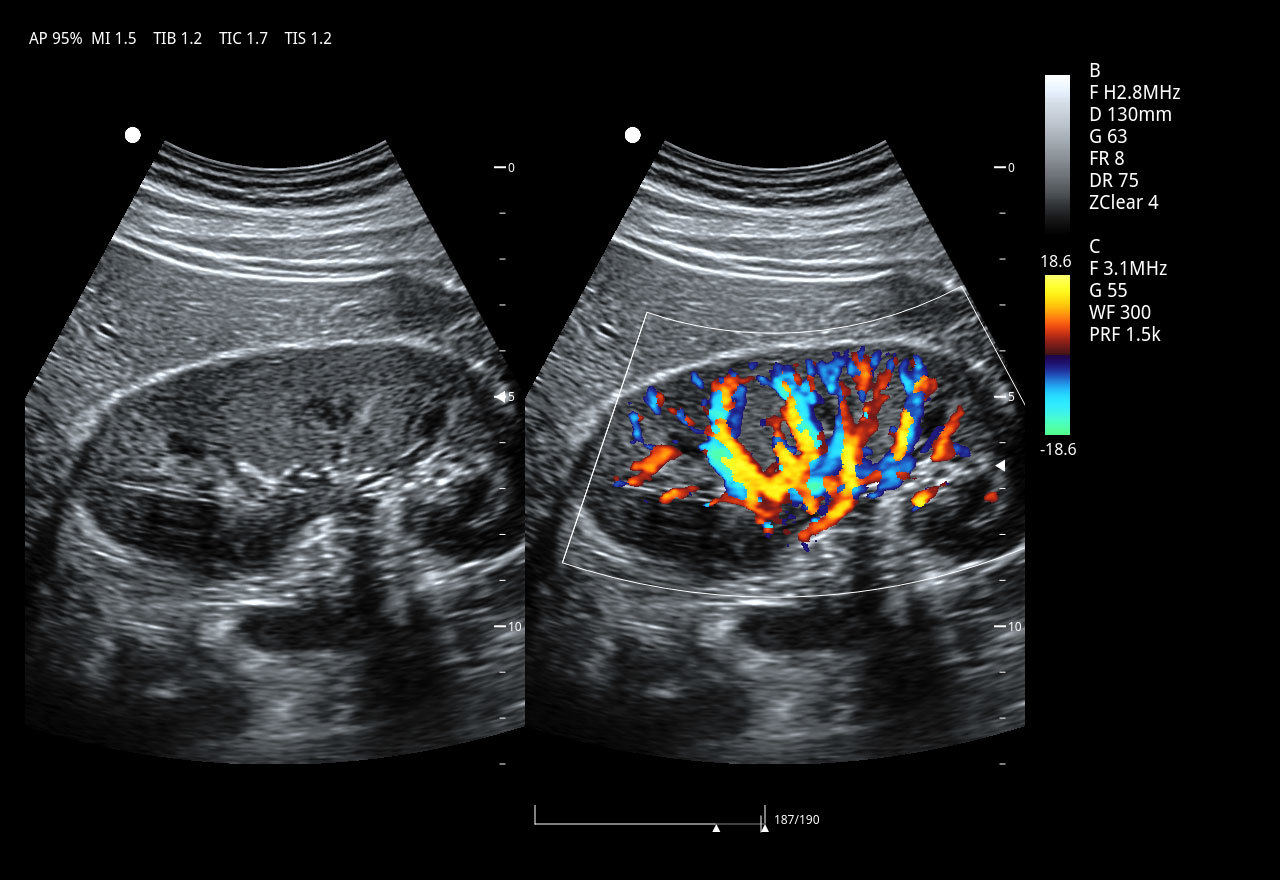

EVORAY USS 20 поддерживает полный набор режимов, востребованных в клинической практике:

• цветовой и энергетический допплер

• импульсно-волновой и постоянно-волновой допплер

• панорамное сканирование и ExFOV (Extended Field of View)

Конвексный датчик 3C5PD

• Рабочая полоса частот: 1,0–7,5 МГц

• Количество элементов: 128

• Радиус кривизны: 50 мм

• Применение: абдоминальные исследования (органы брюшной полости и забрюшинного пространства), общая диагностика.